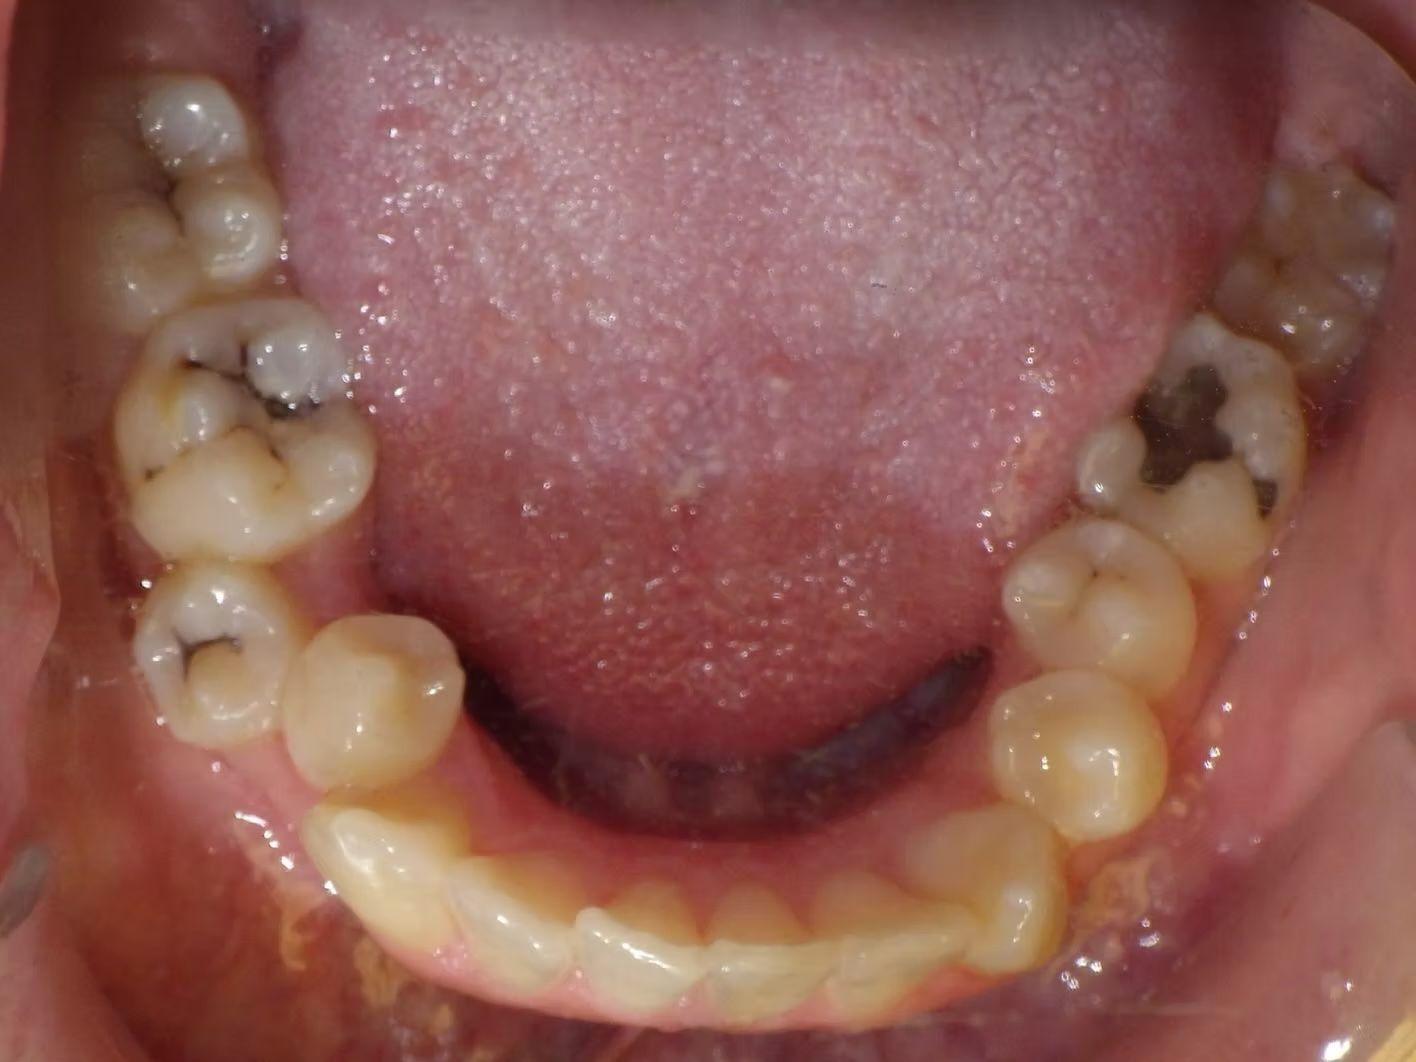

BRIANNA

Brianna's lower left 1st premolar was completely in a brodie bite (outside the normal arch) and her top and bottom teeth were very crowded. Dr. Freedman corrected her bite and crowding without removing any teeth.